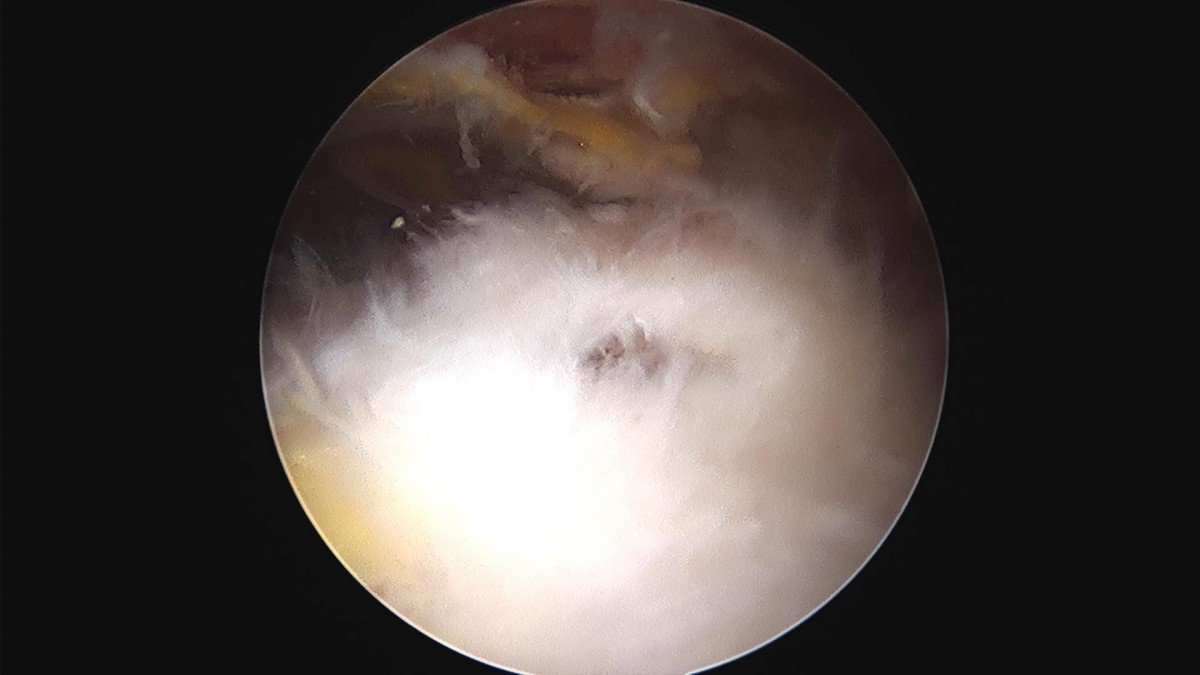

이재상원장님 어깨 회전근개 봉합술 및 견봉하 감압술 정우O 환자

db0e7bbc1426b65f2d696bfef2808102_1663728975_3873.jpg